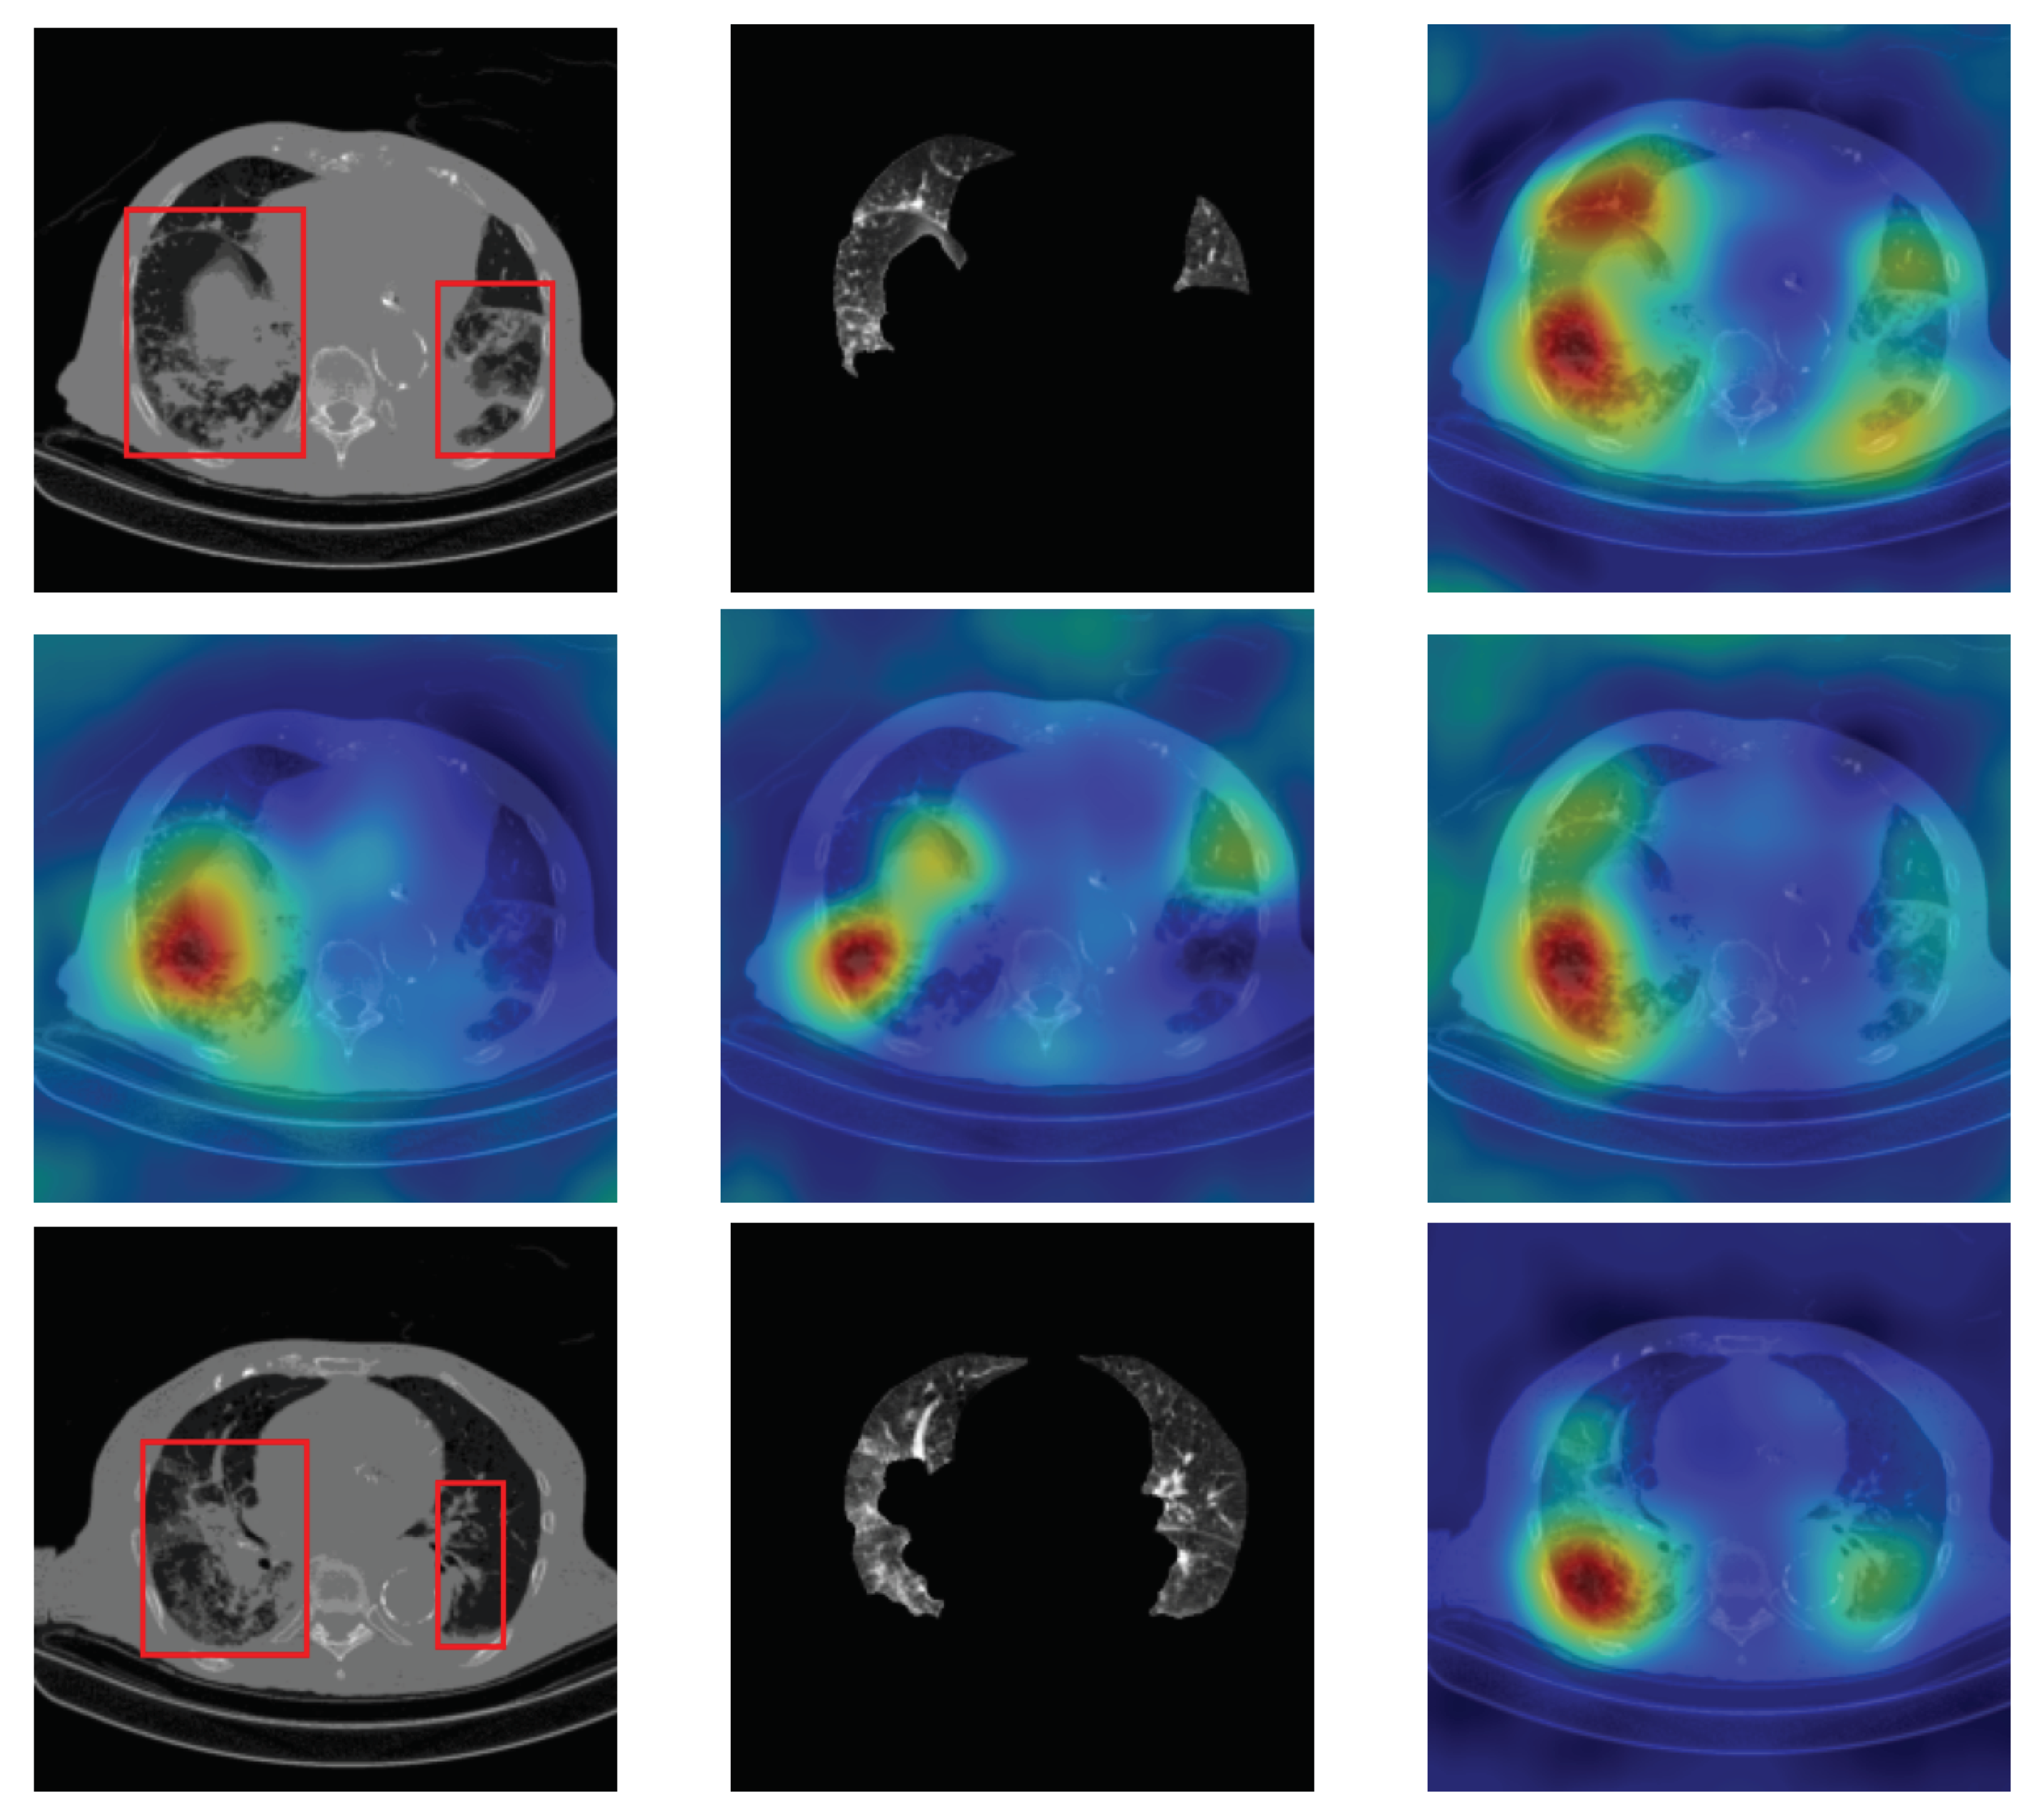

For lung segmentation, we used marker-based watershed segmentation [28], which is based on identifying two markers. The internal marker identifies the lung tissue, and the external marker identifies the outside of the region of interest. The internal marker is obtained by thresholding the image and removing all regions and leaving just the biggest one. The external marker is created by morphological dilation of the internal marker with two different iterations and subtracting the results. A watershed marker is created superimposing the two markers with different gray-scale values. To find the precise border of the lung, the marker-based watershed algorithm is applied on the black strip of the watershed marker and the Sobel gradient image of the original scan. In order not to miss lobes located next to the border regions, a black top-hat operation is performed to re-include those areas and areas surrounding the lung hila. Finally, the segmented lungs mask is obtained by holes closing. Figure 1 shows some examples of the lung segmentation for infected slices with COVID-19 and Cap diseases.

Figure 1.

Lung segmentation examples: the first column shows the input CT scan slice, the second column shows the lungs mask result, and the last column shows the lung segmentation results. The corresponding classes for rows 1 to 3 are COVID-19, COVID-19, and Cap, respectively.

4.4. Segmentation Influence

Stacking segmented lung lobes with the grayscale image proved its efficiency (by comparing the results of Table 1 and Table 2). Despite this considerable improvement, the recognition of Cap slices needs more improvement. Figure 12 shows some segmented slices for COVID-19 and Cap cases. From Figure 12, we notice that the segmented results considered infection parts as lung lobes especially for Cap slices (row 2 and 3 Figure 12). One possible way to improve the performance of our approach is to use a CNN-based approach that were trained on infected slices to segment the lung lobes.

Figure 12.

Segmented lung lobes of infected slices with COVID-19 and Cap. Rows 1, 2, and 3 are for COVID-19, Cap, and Cap slices, respectively.